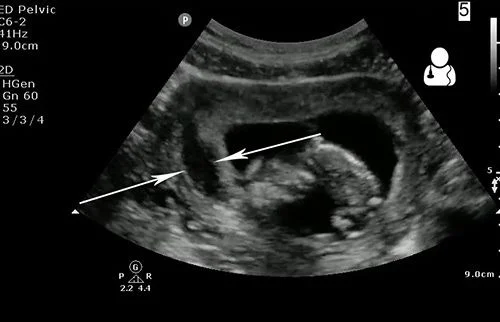

“Navigating the First Trimester: Ultrasound and Anticoagulation Management

Key Sonographic Objectives in the First Trimester

When scanning a patient on anticoagulation, our focus shifts toward identifying early signs of pregnancy failure or maternal complications.

2. Identifying Subchorionic Hemorrhages (SCH)

Anticoagulation therapy can increase the incidence or size of subchorionic bleeds.

- Documentation: Measure the hematoma in three planes.

- Assessment: Note the volume relative to the gestational sac. A hematoma surrounding more than 50% of the sac carries a higher risk of pregnancy loss.

- Clinical Impact: Your report may lead the physician to ‘hold’ or adjust the dosage of anticoagulants.